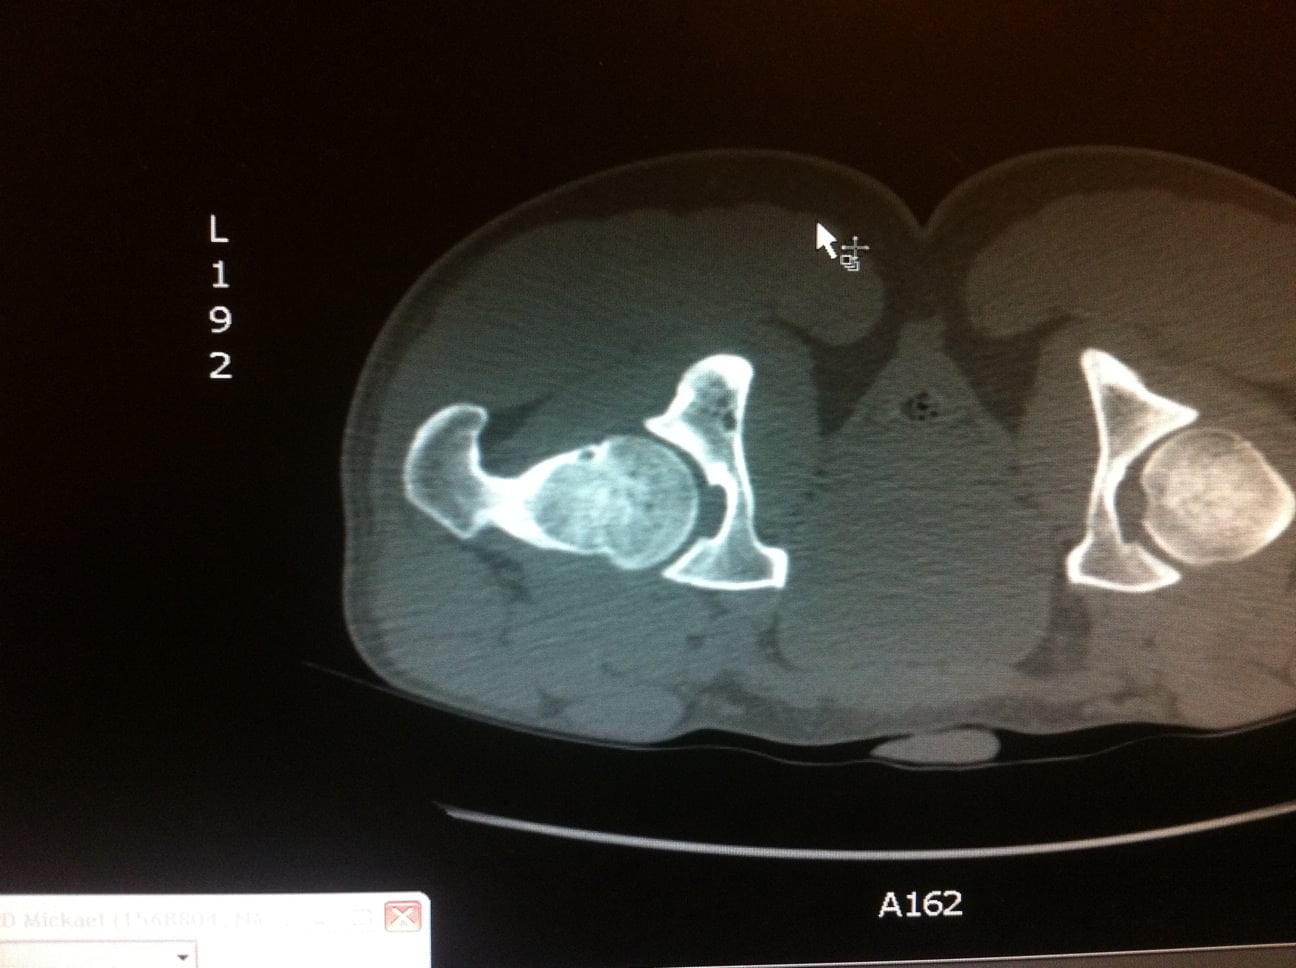

L’Examen est centré sur la région d’intérêt par Acquisition hélicoïdale de Coupes de 1 à 2mm jointives

Le scanner permet de repérer :

Le Nidus = hypodensité à contours nets associé à une hyperdensité calcique linéaire centro-tumorale correspondant à la vascularisation centrale. Une zone hypodense osseuse linéaire au niveau perilésionnel en regard de la condensation est assez spécifique. L’Ostéocondensation périphérique est homogène et peut provoquer une réaction périoste.